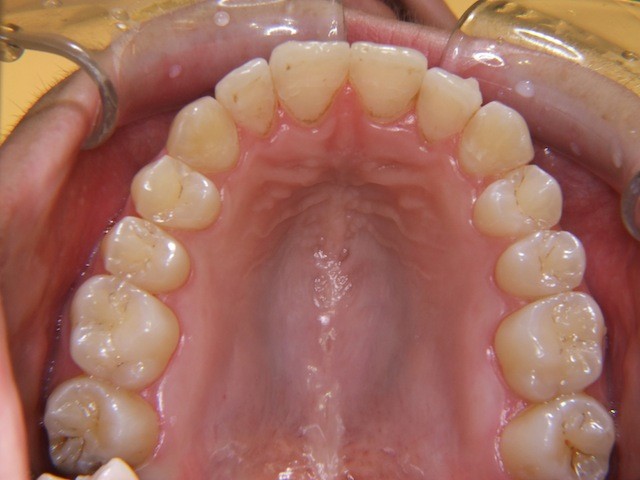

Beispiel einer Engstandsbehandlung bei einem Erwachsenen mit Invisalign

Vorher ----------------------------------- Nachher

Bilderserie Invisalignbehandlung Oberkiefer mit Stabilisierungsdraht am Schluss. Man beachte die Ansammlung von Belägen und Verfärbungen infolge Nischenbildung am Zahn der am meisten im Engstand steht.